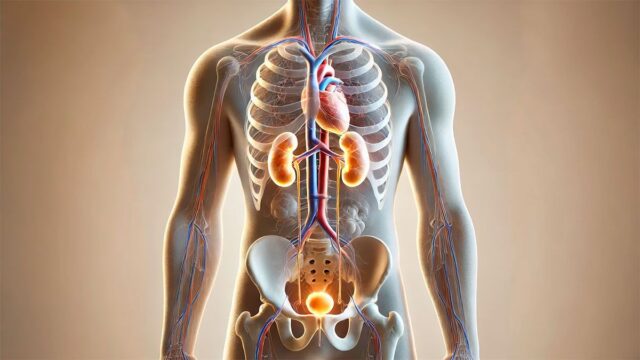

El cuerpo humano depende de mecanismos precisos para funcionar correctamente.

Uno de ellos es el equilibrio de electrolitos, un grupo de minerales que facilitan procesos vitales como la hidratación, la función muscular y la transmisión nerviosa.

Los electrolitos son sustancias que, que se disuelven en el agua de la agencia, se separan en iones de carga eléctrica. Entre los principales se encuentran sodio, potasio, calcio y magnesio.

Estos minerales permiten el paso de impulsos eléctricos y son indispensables para la comunicación entre las células nerviosas y musculares.

El sitio MedlinePlus, de la Biblioteca Nacional de Medicina de los Estados Unidos, explica que cada uno cumple con funciones específicas: el sodio y el cloruro predominan fuera de las células, mientras que el potasio lo hace dentro y todos trabajan juntos para mantener el equilibrio hídrico, el pH y el metabolismo energético.

La Academia Española de Nutrición y Dietética detalla que, entre sus múltiples roles, los electrolitos son responsables de regular el movimiento de agua dentro y fuera de las células, garantizando una contracción muscular adecuada, incluidos los latidos cardíacos, y mantener la transmisión de impulsos eléctricos en el sistema nervioso.